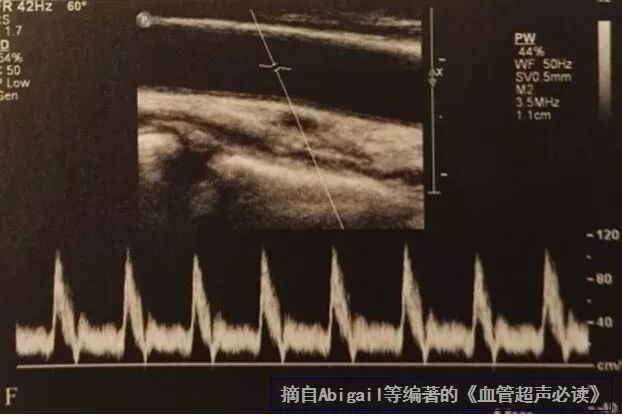

取样容积的大小

上图中那个类似“=”的小框框就是所谓的取样容积,也就是说落在这个框里的信号才会被采集,一般认为取样容积的大小为血管直径的50-70%,也就是大概2/3左右。